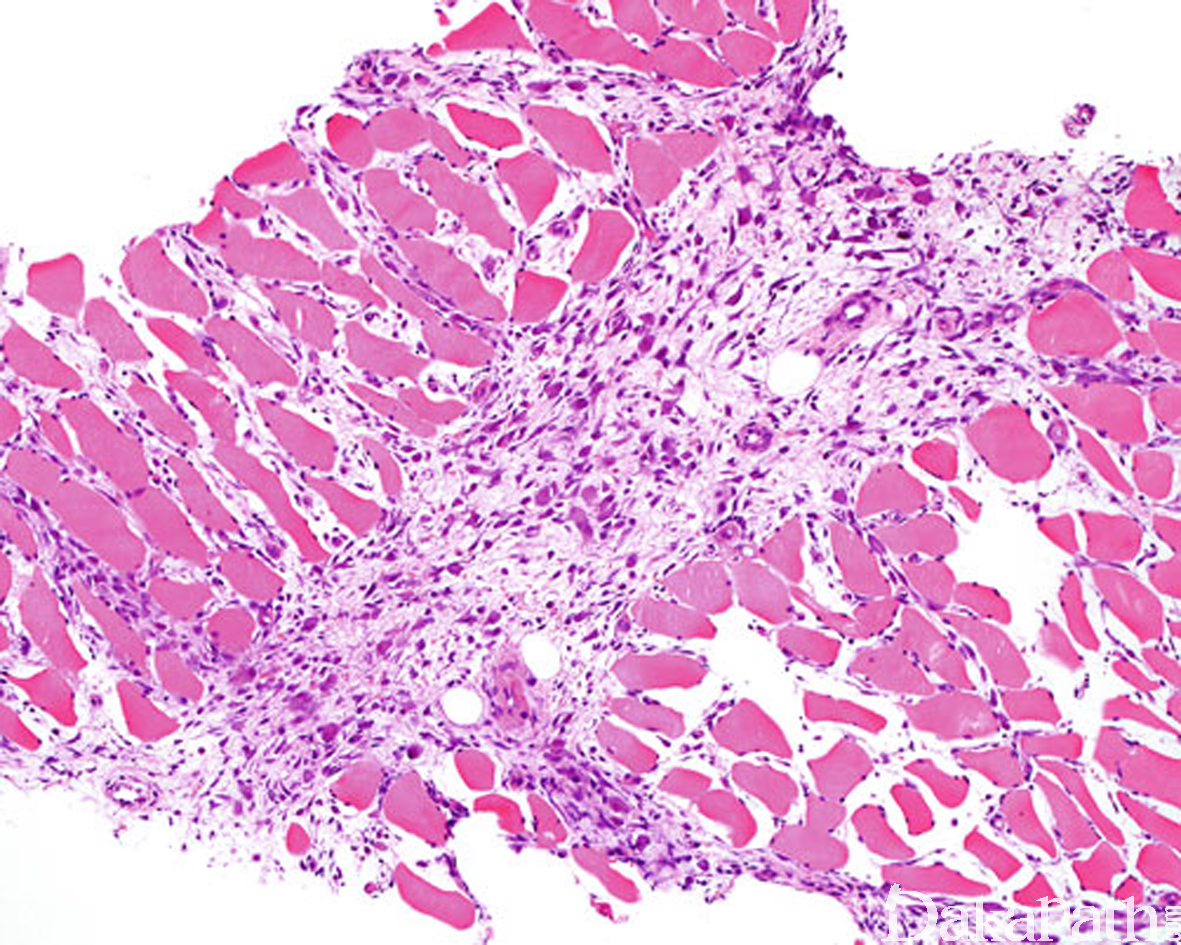

病变穿插于横纹肌纤维之间,在横切面上常形成“棋盘”样,不累及横纹肌纤维本身;

好发于中老年人,少数发生于儿童,常见于四肢,主要累及骨骼肌;